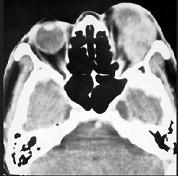

问题 男性45岁,左眼疼痛伴视力下降一个多月,左眼明显外突,CT扫描如图所示,最可能诊断为 ( )

选项 A、眶内结核 B、眶内转移瘤 C、眶内血管瘤 D、眶内纤维瘤 E、左侧眶内炎性假瘤

答案 E